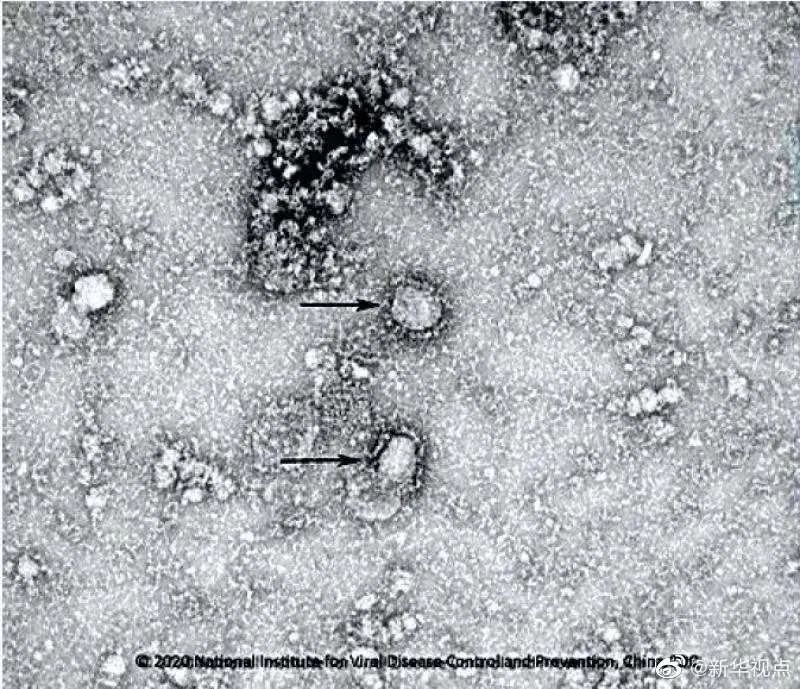

新冠病毒电镜照片